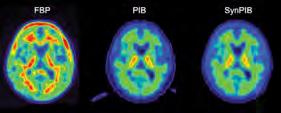

Inside the brain, Alzheimer’s is characterized by the growth of amyloid plaques, clumps of abnormal proteins that form in the gaps between neurons. New treatments such as lecanemab target these plaques. To track how these drugs are working, subjects in clinical trials are injected with a radioactive tracer that sticks to the amyloid so that it shows up on a PET scanner.

There are five different FDA-approved tracers, all with

36 S UMMER 2024

different properties, and different clinics use different tracers, making it hard for researchers to compare data. AI can help.

Teresa Wu, a professor in ASU’s School of Computing and Augmented Intelligence and health solutions ambassador in the College of Health Solutions, uses AI to harmonize PET scans taken with different types of tracers.

Wu’s model generates what a brain scan taken using one type of tracer would look like if it had been taken with a different one, enabling easier comparison and research.

“If you want to make use of imaging data to support medical

decisions, there is a hurdle to overcome,” she says. “You cannot just take the data from different sources and dump it in your deep-learning model. You have to make sure it’s clinically relevant and usable.”

Doing that opens a wealth of new opportunities for using AI to improve diagnosis.

Teresa Wu and team use AI to combine PET scans that use different tracers. From left: FBP tracer PET scan, PIB tracer PET scan, AI-Generated PIB tracer PET.